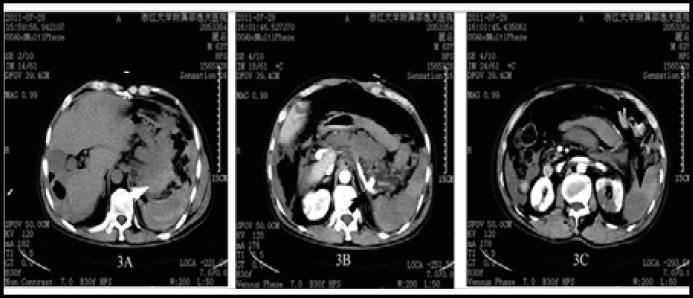

Rupture of splenic artery aneurysm remains an uncommon cause of hypovolemic shock although it is the third most common intra-abdominal aneurysms. It is difficult to diagnosis timely and entails a significant morbidity and mortality. We present three uncommon cases of bleeding from upper gastrointestinal tract as a result of rupture of splenic artery aneurysm to stomach in patients with liver cirrhosis or infectious endocarditis. We also reviewed the literature and these case reports highlighted that rapid resuscitation, diagnostic imaging, surgical consultation, and alternatively transarterial embolization were the priorities in the management. Early diagnosis and intervention for ruptured splenic artery aneurysm are crucial for patient's survival; therefore, it must be kept in mind as feasible etiology of life-threatening gastrointestinal bleeding, especially in patients with underlying liver cirrhosis or infective endocarditis.

脾动脉瘤破裂虽然是引起低血容量性休克的第三大常见腹腔内动脉瘤,但仍是一种罕见的原因。它很难及时诊断,导致发病率和死亡率显著增加。我们报告了 3 例因肝硬化或感染性心内膜炎导致胃脾动脉瘤破裂出血至上消化道的罕见病例。我们还回顾了文献,这些病例报告强调了快速复苏、诊断成像、外科咨询和选择性经动脉栓塞是治疗的重点。脾动脉瘤破裂的早期诊断和干预对患者的生存至关重要;因此,对于危及生命的胃肠道出血,特别是在有基础肝硬化或感染性心内膜炎的患者,应将其视为可能的病因。